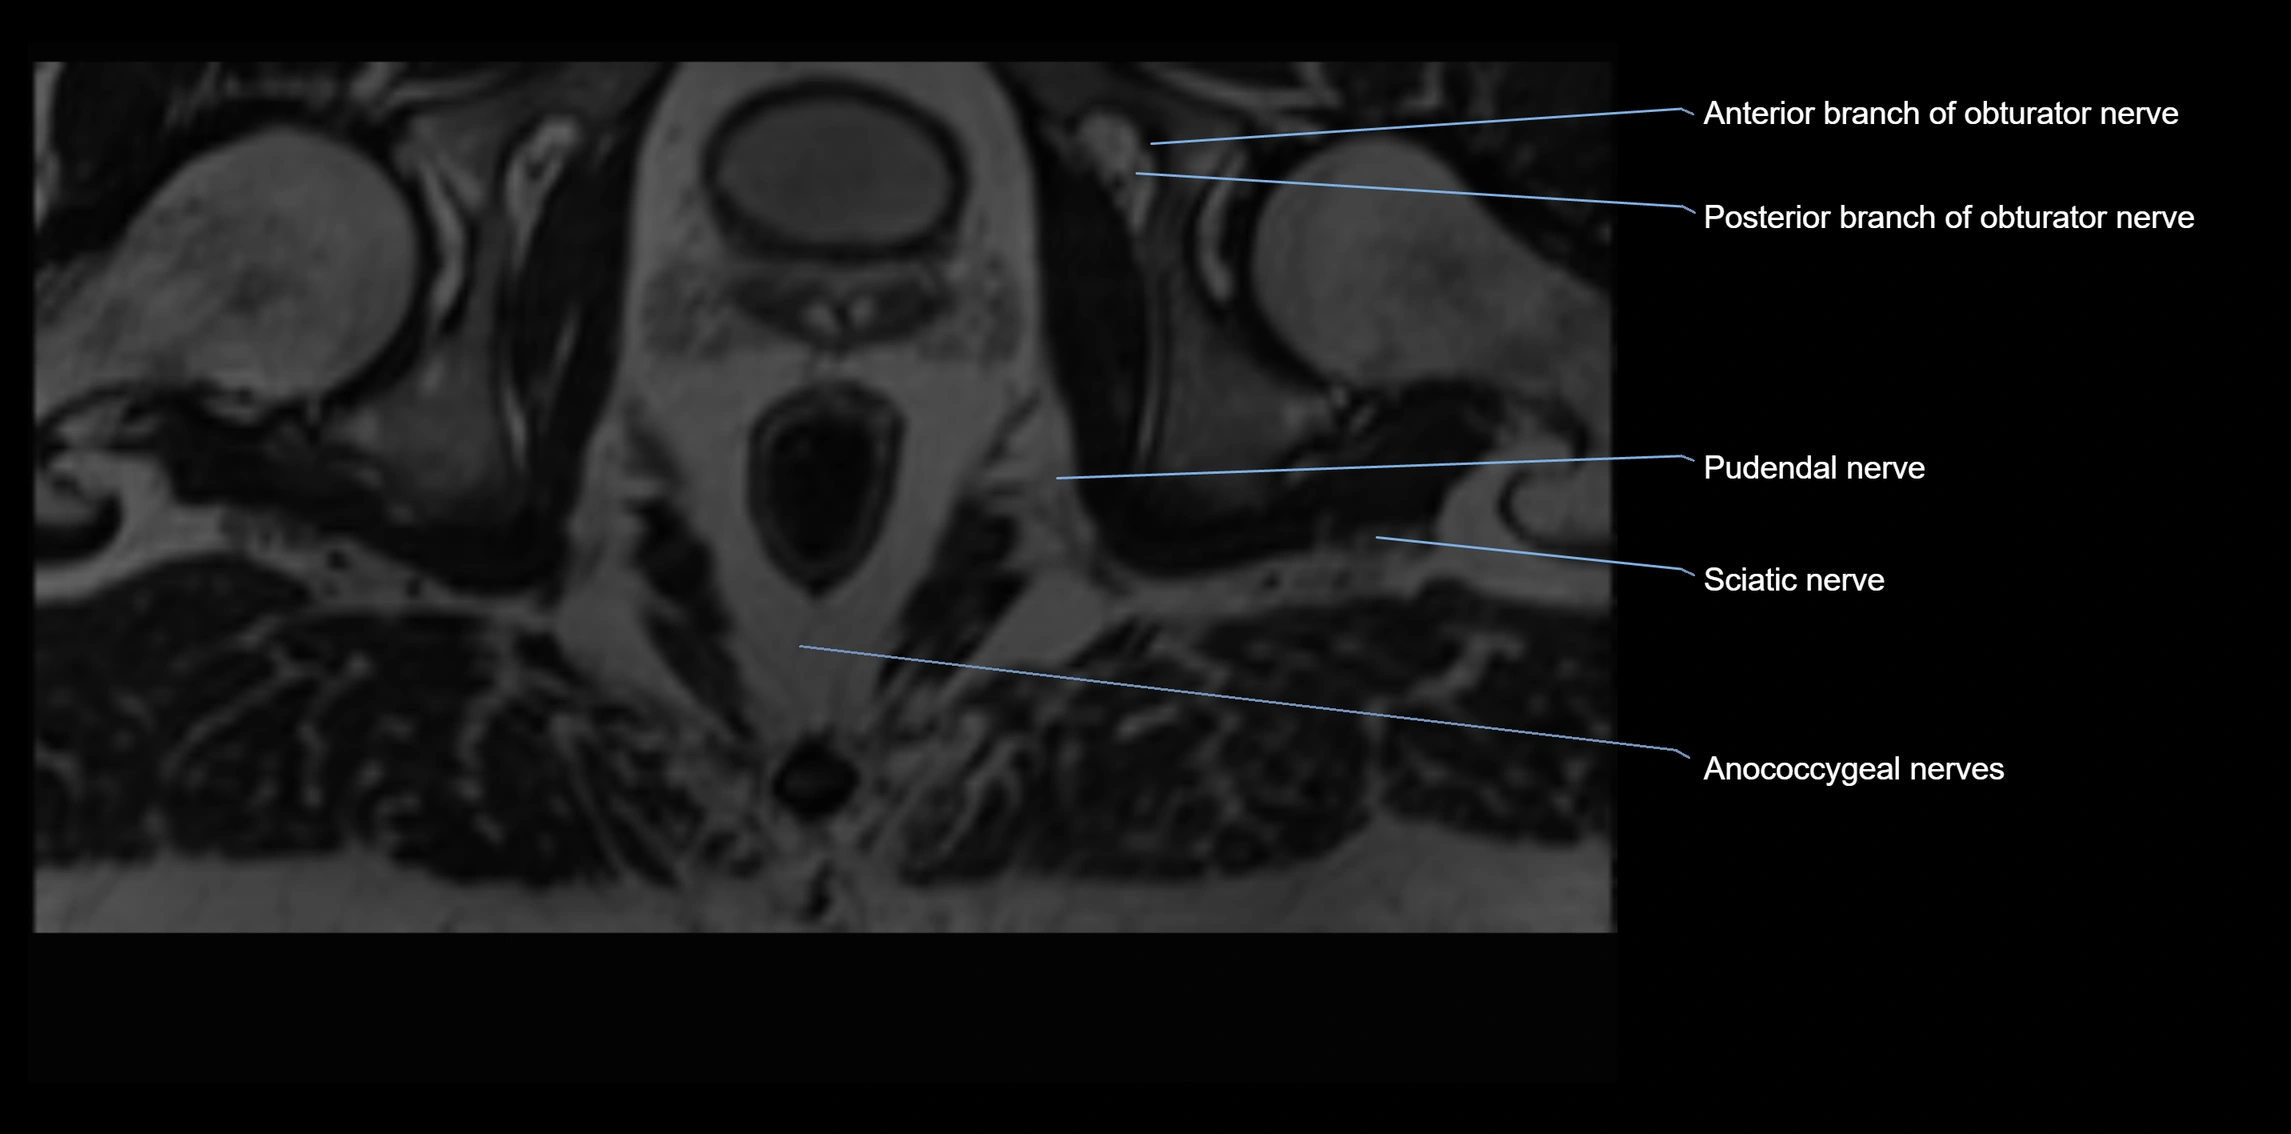

MRI Appearance

T1-weighted images:

• Nerve appears as a very thin low-to-intermediate signal intensity structure

• Surrounded by bright fat, aiding visualization

T2-weighted images:

• Nerve shows intermediate to mildly hyperintense signal compared to muscle

• Pathological involvement appears brighter

STIR (Short Tau Inversion Recovery):

• Normal nerve appears dark

• Inflamed or entrapped nerve appears bright hyperintense

T1 Fat-Sat Post-Contrast:

• Normal nerve enhances minimally

• Pathologic nerve (neuritis, entrapment, tumor infiltration) shows focal or diffuse enhancement

3D T2 SPACE / CISS:

• Nerve appears intermediate to mildly hyperintense compared to muscle

• Surrounded by bright fat or CSF, improving visualization

• Best sequence for mapping small pelvic nerves such as the anococcygeal

MRI image

image